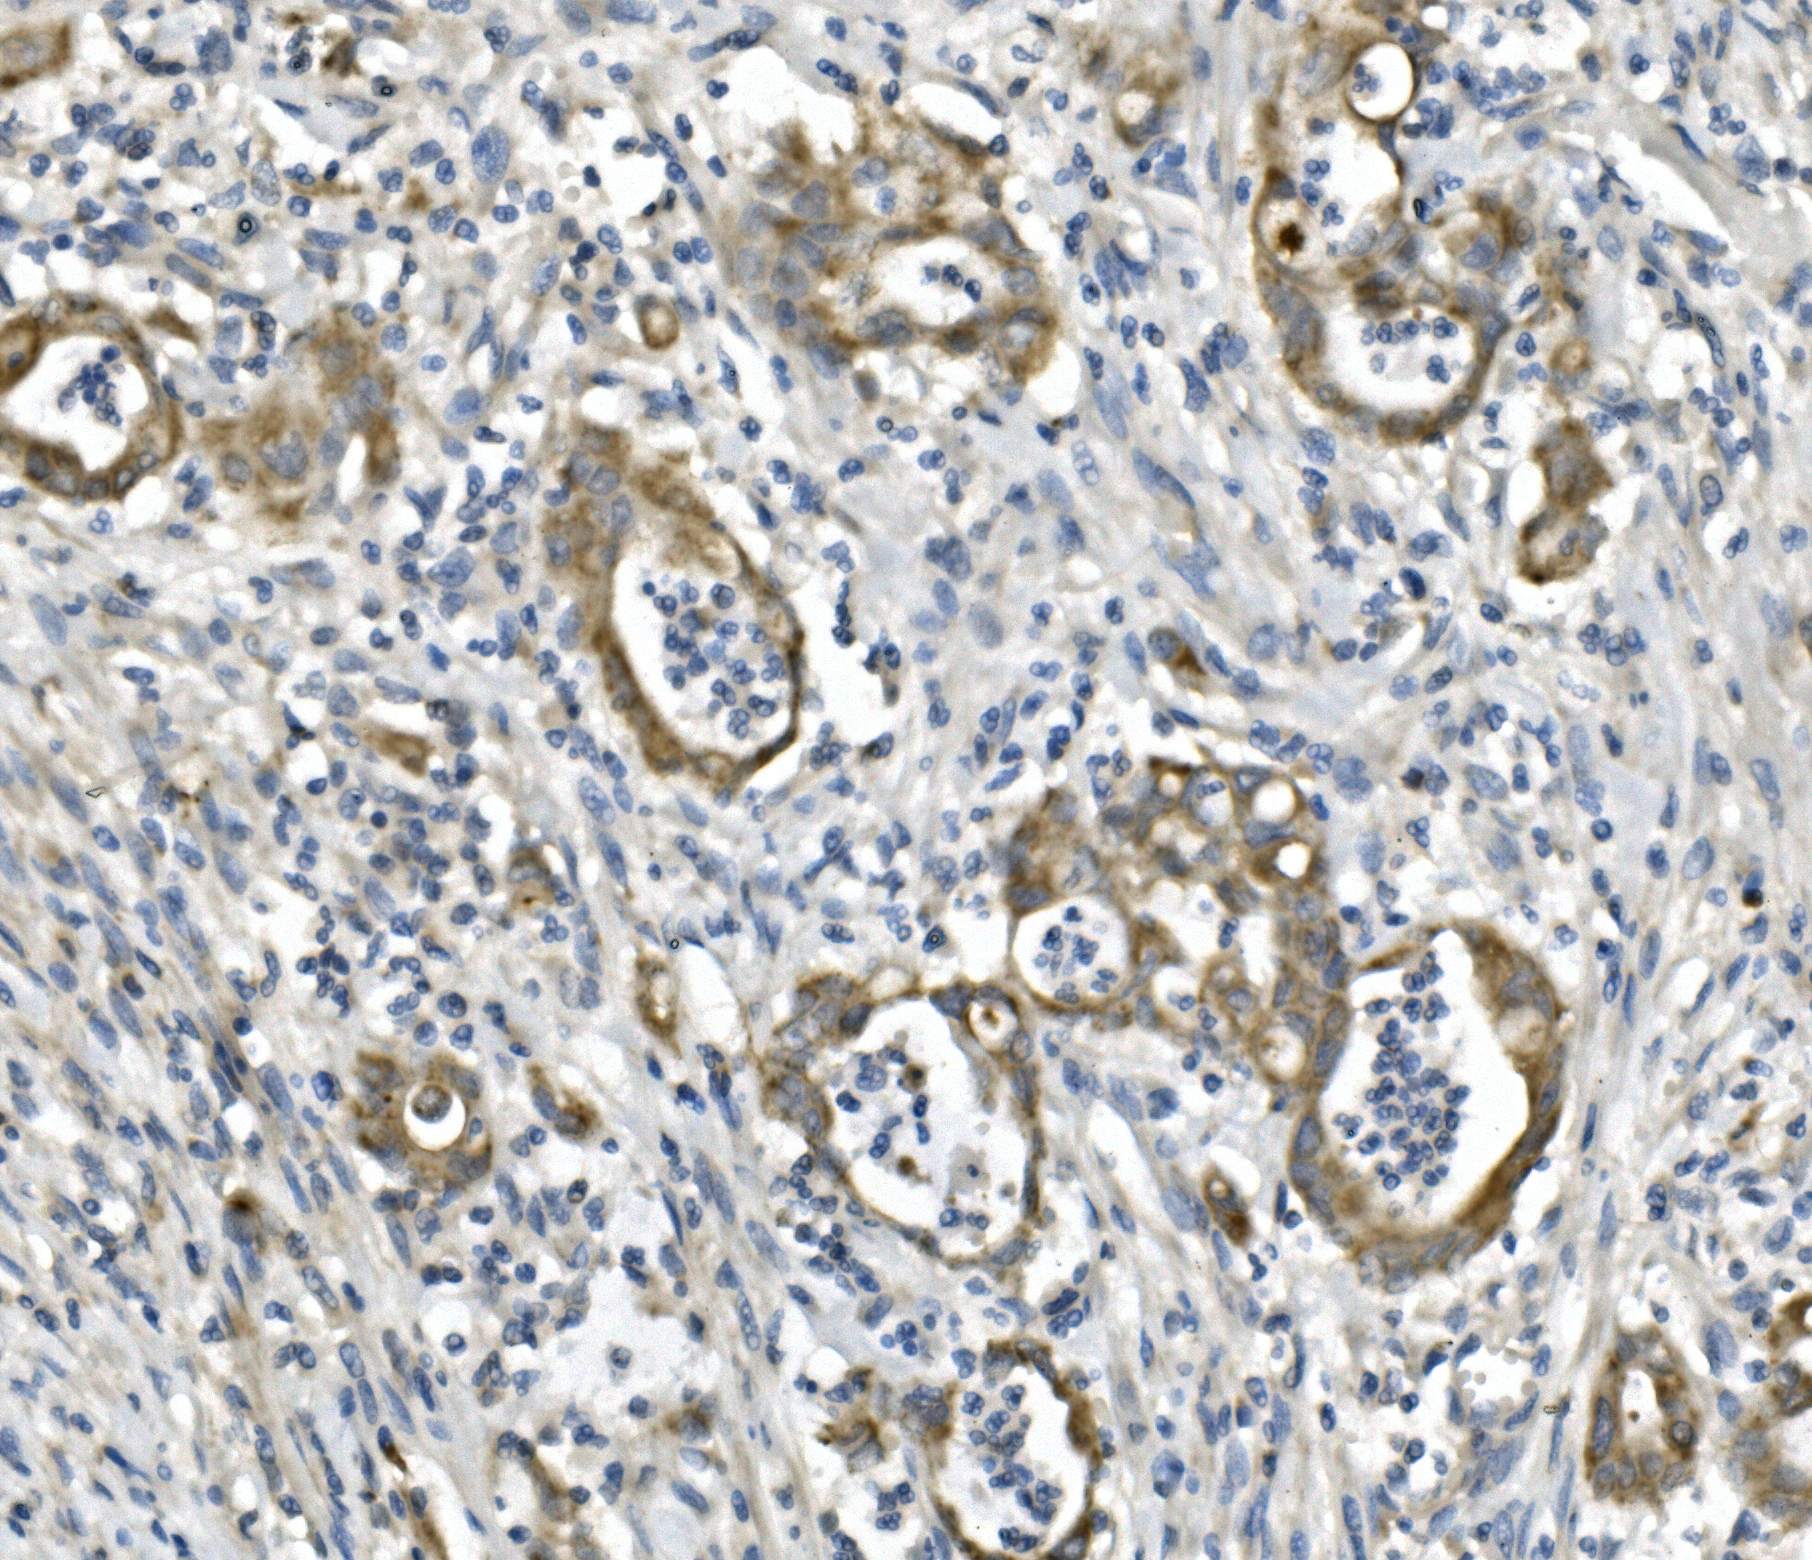

IHC analysis of CXCR2 using anti-CXCR2 antibody (A00455-1).

CXCR2 was detected in a paraffin-embedded section of human rectal cancer tissue. Biotinylated goat anti-rabbit IgG was used as secondary antibody. The tissue section was incubated with rabbit anti-CXCR2 Antibody (A00455-1) at a dilution of 1:200 and developed using Strepavidin-Biotin-Complex (SABC) (Catalog # SA1022) with DAB (Catalog # AR1027) as the chromogen.